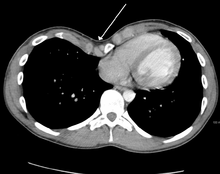

Cross sectional scan of a chest with pectus excavatum

Pectus excavatum is initially suspected from visual examination of the anterior chest. Auscultation of the chest can reveal displaced heart beat and valve prolapse. There can be a heart murmur occurring during systole caused by proximity between the sternum and the pulmonary artery.[17] Lung sounds are usually clear yet diminished due to decreased base lung capacity.[18]

Many scales have been developed to determine the degree of deformity in the chest wall. Most of these are variants on the distance between the sternum and the spine. One such index is the Backer ratio which grades severity of deformity based on the ratio between the diameter of the vertebral body nearest to xiphosternal junction and the distance between the xiphosternal junction and the nearest vertebral body.[19] More recently the Haller index has been used based on CT scan measurements. An index over 3.25 is often defined as severe.[20] The Haller index is the ratio between the horizontal distance of the inside of the ribcage and the shortest distance between the vertebrae and sternum.[21]